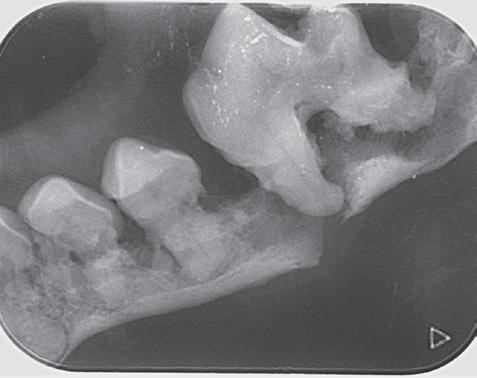

Fracturas dentales

Es una de las complicaciones perioperatorias más frecuentes y puede producirse en el diente objeto de la extracción (en la corona o en la raíz) o en los dientes contiguos si se realiza un uso incorrecto del instrumental (figuras 1 y 2).

En la fractura del diente intervienen diversos factores, como son:

• La presencia de un tratamiento endodóncico previo que ha debilitado el diente.

• Fracturas coronarias previas en las que disponemos de menos corona para poder ejercer fuerza con el fórceps.

• Anquilosis de la raíz dentaria, raíces curvas o divergentes con una disposición anatómica diferente que modifica la tracción.

• Acceso inadecuado o error en la técnica de exodoncia por falta de experiencia.

Si la fractura se produce en la corona dental, se debe normalmente a una fuerza excesiva producida con los elevadores o con el fórceps dental.

Las fracturas radiculares son una complicación habitual (figura 3). Los factores que influyen con más frecuencia son: técnica incorrecta de exodoncia, daños preexistentes en la estructura de la raíz y variaciones en la anatomía normal. Normalmente, cuando se produce una fractura de la raíz, se produce un sonido y tacto particular. Además, cuando se extrae el diente, si palpamos el borde de la raíz este es irregular, y no liso y redondeado.

Si la fractura se produce en la cara coronal de la raíz, se debe introducir un luxador en el espacio periodontal para continuar con la exodoncia. Si la fractura se produce dentro del alvéolo, la extracción se hace más complicada. Es muy importante en estos casos trabajar con radiología dental para visualizar el tamaño, la localización y la forma del resto radicular. Se recomienda realizar una alveolectomía (eliminación de porciones específicas de hueso alveolar que faciliten el abordaje) y el uso de la jeringa multifunción. Una vez localizado el resto radicular, se podrá introducir un luxador en el ligamento periodontal para continuar con la exodoncia. En los casos en los que existe anquilosis radicular, en los cuales es imposible insertar un luxador en el espacio del ligamento periodontal, se puede utilizar una fresa de diamante redonda o cónica para crear un espacio alrededor del fragmento de la raíz.

Se produce sobre todo en perros de razas pequeñas y con un estado avanzado de enfermedad periodontal, por ello es importante la realización de radiografías dentales previa a la extracción (figuras 5 y 6).

Existen dos zonas en la mandíbula más susceptibles de sufrir fracturas:

• Cuerpo de la mandíbula a nivel del primer molar, zona que presenta menor

resistencia debido a un menor grosor del hueso y menor altura de la mandíbula en la raíz distal comparado con otras zonas.

• Hueso alveolar lingual del canino mandibular de perros pequeños y gatos, debido a que el grosor del hueso alveolar es de unos 2-3 mm.

Figura 5. Radiografía preoperatoria en la que se observa el primer molar mandibular (409) con gran pérdida de estructura ósea debido a enfermedad periodontal. En la extracción de este diente existe un gran riesgo de fractura mandibular.